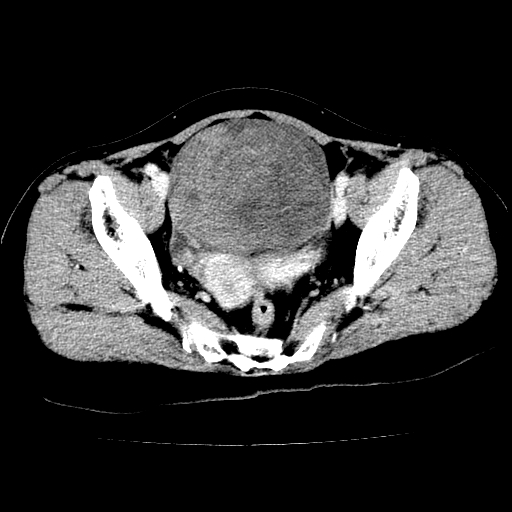

标题: CT24785:女,62岁,发现下腹部肿物半年。 [打印本页]

标题: CT24785:女,62岁,发现下腹部肿物半年。

女,62岁,发现下腹部肿物半年,下腹部不适。

老年女性患者,盆腔囊实性占位,ct增强不均匀强化,未见壁结节,未见腹水及盆腔积液,考虑附件囊腺瘤可能性大!